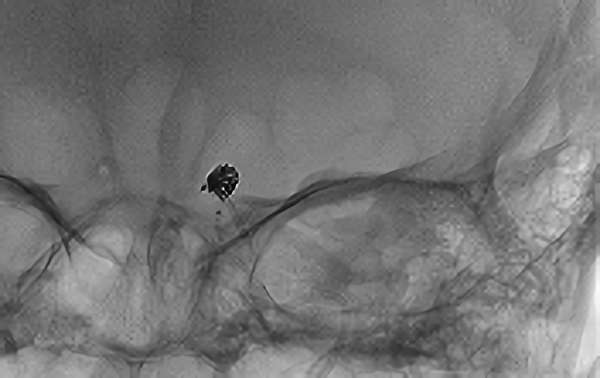

前交通動脈瘤

No.1627 手術中